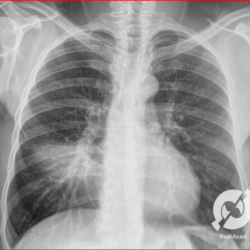

Os agentes etiológicos infecciosos são variados (bactérias, vírus, fungos, parasitas…), mas o que ocorre nos pulmões durante uma infecção por qualquer tipo de agente é a substituição do ar alveolar por secreção (pus, muco, eventualmente sangue ou necrose…) e com isso a manifestação radiográfica vai ser a mesma já que todas estas secreções apresentam a mesma densidade radiográfica: partes moles.

E o nome dado a esta alteração radiográfica que corresponde à substituição do ar alveolar por líquido é a consolidação alveolar.

Uma consolidação alveolar é, por definição, uma opacidade (imagem densa, branquinha) homogênea ou às vezes heterogênea (pela presença de calcificações ou cavidades), de limites mal definidos, exceto quando toca a pleura da parede ou das cissuras pulmonares. É um termo usado tanto em radiografia, como em tomografia computadorizada. Na tomografia, um outro termo é usado: vidro fosco, que é uma opacidade (branquinha mas não tanto como a consolidação), que borra o pulmão mas deixa ver os vasos de permeio (igual bigode de adolescente: dá pra ver todo o fundo).

Nós vamos mostrar aqui um pequeno apanhado de pneumonias de variados agentes, em diversos segmentos e lobos pulmonares, com extensões variadas. O objetivo é identificar o padrão radiológico de consolidação alveolar e não determinar o agente infeccioso, isso vai ser assunto para mais adiante. Aliás já antecipo que é fundamental saber localizar a lesão, porque alguns destes bichos gostam de determinados segmentos, alguns tumores também têm as suas preferências, então localização é fundamental. Se localização não fosse importante, um apartamento na beira do mar sairia o mesmo preço de um apartamento de frente pra BR-101, concordam?